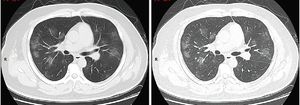

وجدت إحدى الدراسات في الصين أن التصوير الطبقي المحوسب أظهر عتامة الزجاج مغشي في 56 ٪ ، ولكن 18 ٪ لم يكن لديها نتائج إشعاعية. تم قبول 5 ٪ في وحدات العناية المركزة ، و 2.3 ٪ بحاجة إلى دعم التهوية الميكانيكية ، وتوفي 1.4 ٪.[36] عتامات الزجاج المغشي الثنائي والمحيطي هي أكثر نتائج التصوير المقطعي المحوسب النموذجي.[37] التصلد والعتامة الخطية وعلامة الهالة العكسية هم نتائج إشعاعية أخرى.[37] في البداية ، تقتصر الآفات على رئة واحدة ، ولكن مع تقدم المرض ، تظهر المؤشرات في كلا الرئتين في 88٪ مما يسمى "المرضى المتأخرون" في مجموعة الدراسة (المجموعة الفرعية التي كان الوقت بين ظهور الأعراض والتصوير الطبقي المحوسب للصدر 6-12 يومًا).[37]